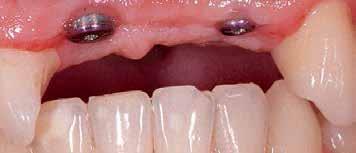

A bench scan (Medit T-710 Tabletop Scanner) of the cast and preoperative CBCT (3D Accuitomo 170) was made for each participant for the construction of a CAD CAM surgical guide. The implant was planned to engage the palatal wall, avoid pressure on the labial plate of the bone, and be 1-mm apical to the crest. A fully guided tooth-supported surgical guide was designed and then printed in clear acrylic resin (Dental SG Resin; Formlabs) by using a 3D printer (Form2; Formlabs). (fig 2)

A systemic antibiotic (2g amoxicillin-clavulanic acid, per-orally) was administered to the patients 1 hour prior to the procedure. The patient’s mouth was rinsed with a solution of chlorhexidinedigluconate 0.2% for 2 minutes. After surgical guide printing, the tooth was extracted and the implant placed (IDI implant Implants Di usion International 23/25) following implant placement protocol using a fully guided CAD CAM surgical guide. 14 (fig 3,4,5)

Figure 5: Fully guided implant placement through the surgical guide using spoons. The implant was inserted at the planned position.